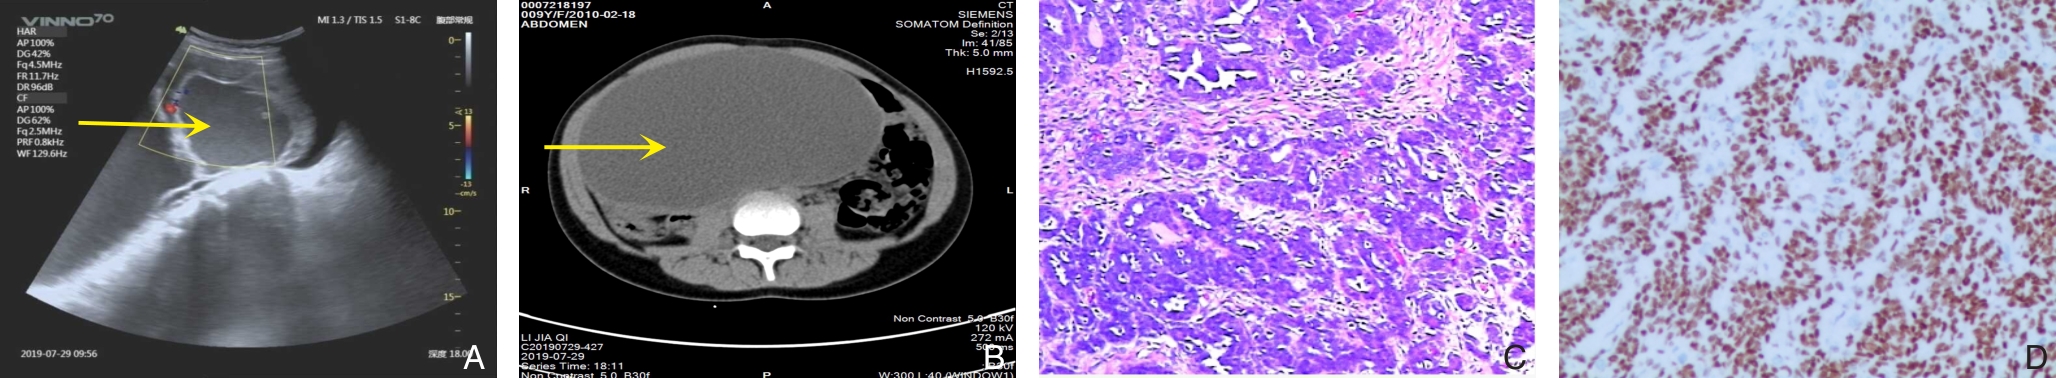

• China Journal of General Surgery, 2026, 35(1):187-191.

Abstract:背景与目的 原发性结肠黏膜黑色素瘤极为罕见,恶性程度高,易发生淋巴及远处转移,预后不佳,临床诊断困难。本文报告1例结肠回盲部原发性黏膜黑色素瘤病例,并结合文献复习,总结其临床特征、诊断要点、治疗策略及预后情况,以提高对该罕见疾病的认识。方法 回顾性分析1例经手术及病理证实的结肠回盲部原发性黏膜黑色素瘤患者的临床资料,包括临床表现、影像学及内镜特征、病理与免疫组化结果、分子检测结果、治疗经过及随访情况,并结合相关文献进行综合分析。结果 患者为52岁女性,2023年11月7日因“间断性右下腹痛3个月”入院。腹部增强CT提示回盲部占位并周围淋巴结肿大;肠镜见巨大结节状肿物充满肠腔,活检提示恶性黑色素瘤。行右半结肠切除术(D2)。术后病理示肿瘤侵犯黏膜层及深肌层,伴脉管内瘤栓,淋巴结转移5/20。免疫组化示S-100、SOX10、Melan-A及HMB45阳性,Ki-67约50%。基因检测提示BRAFV600E突变。术后患者拒绝辅助治疗。术后16个月发现肠系膜区淋巴结转移,23个月出现颈部淋巴结转移,目前随访24个月,仍存活并持续随访。文献复习显示,该病多见于中老年女性,临床表现缺乏特异性,确诊依赖病理及免疫组化,手术切除为无远处转移患者的主要治疗方式。结论 结肠回盲部原发性黏膜黑色素瘤罕见且侵袭性强,早期诊断困难,易发生淋巴转移。确诊需排除转移性黑色素瘤并结合免疫组化及分子检测结果。对于无远处转移患者,根治性手术切除是首选治疗方式,分子靶向治疗及免疫治疗可能成为改善预后的重要方向。